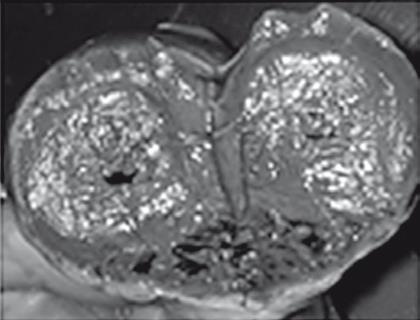

Иллюстрация к книге — Неалкогольная жировая болезнь печени [i_041.jpg]

Хронический стеатогепатит